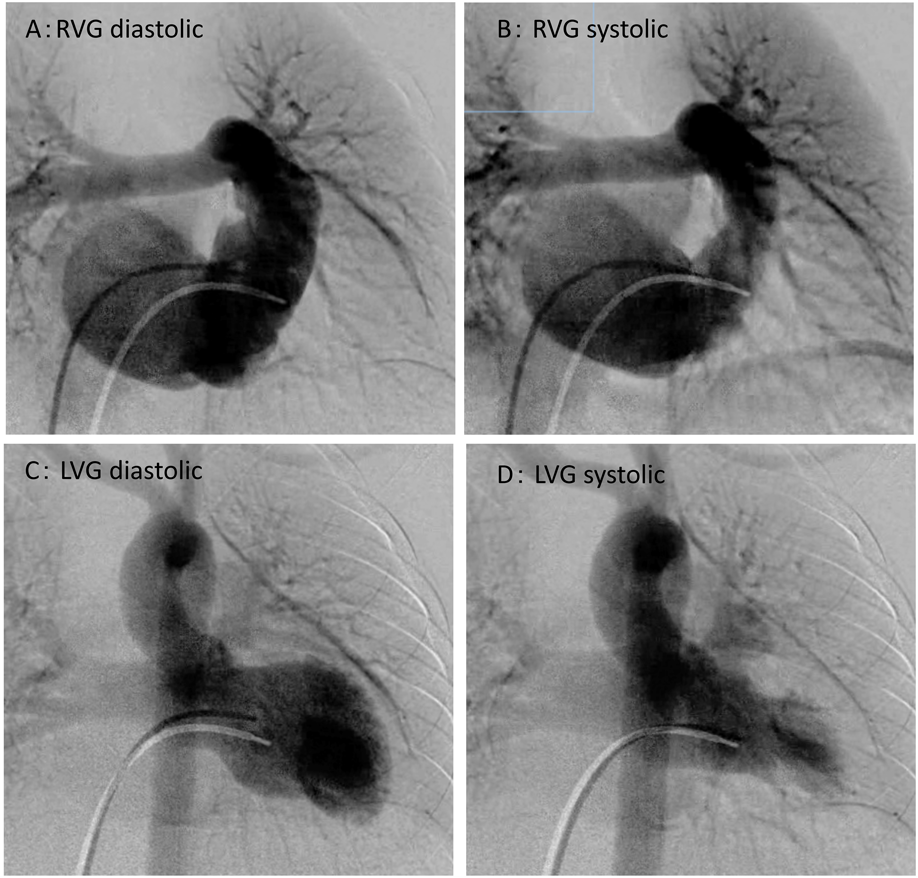

In addition, cardiac catheterization and angiocardiography were performed to examine her heart in detail (Fig. 1, Table 1).

A: Right ventricular diastolic phase. The right ventricle is bipartite where muscle loss occurred. B: Right ventricular systolic phase, significant tricuspid regurgitation was detected. C: Left ventricular diastolic phase. D: Left ventricular systolic phase.

Right ventriculography showed hypoplasia with an end-diastolic right ventricular volume of 45 mL (58% of normal). The diagnosis was isolated hypoplasia of the bipartite right ventricle, which did not affect the muscle. Although we were not able to confirm the shunt between the right and left atrium, the left ventricular end-diastolic volume was 77 mL (99% of normal), and the ejection fraction was 65%.